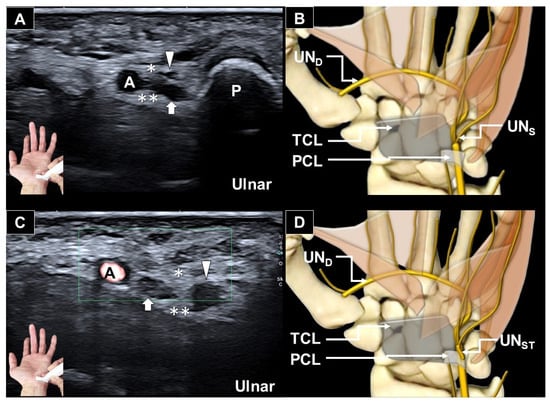

Ultrasonograhic Identification of the Entrapment of a Transligamentous Sensory Branch of the Ulnar Nerve

by Wei-Ting Wu, Ke-Vin Chang and Levent Özçakar

Diagnostics 2026, 16(3), 405; https://doi.org/10.3390/diagnostics16030405 - 27 Jan 2026

Abstract

Anatomical variations of the ulnar nerve at the wrist are uncommon and may lead to diagnostic confusion or iatrogenic injury if unrecognized. We present an ultrasound-based identification of a rare transligamentous ulnar nerve sensory branch entrapment in an elderly male with chronic ulnar-sided [...] Read more.

Anatomical variations of the ulnar nerve at the wrist are uncommon and may lead to diagnostic confusion or iatrogenic injury if unrecognized. We present an ultrasound-based identification of a rare transligamentous ulnar nerve sensory branch entrapment in an elderly male with chronic ulnar-sided hand paresthesia. High-resolution ultrasonography revealed an aberrant sensory branch deviating from the ulnar nerve, piercing the palmar carpal ligament, and coursing superficially rather than entering Guyon’s canal. Further assessment demonstrated focal nerve flattening within the ligament with proximal enlargement, consistent with entrapment. This case highlights the value of ultrasound in detecting rare peripheral nerve variants and their entrapments. Therefore, it is also noteworthy to extend the sonographic evaluation beyond conventional entrapment sites at the wrist. Full article

(This article belongs to the Section Medical Imaging and Theranostics)

Show Figures

Figure 1